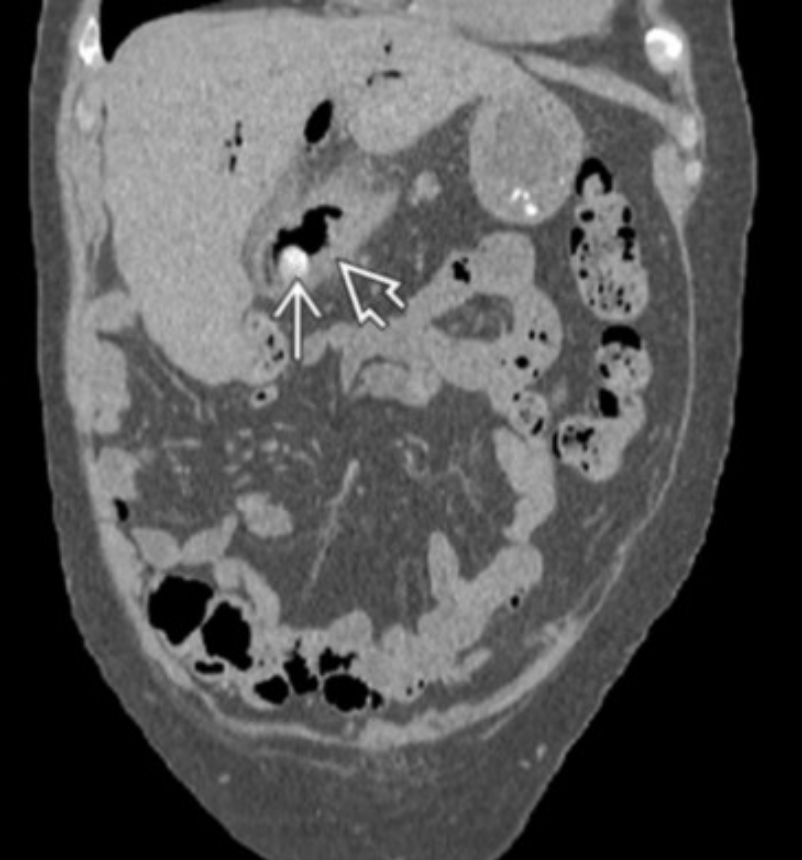

Dx?

Dx: type 4A choledochal cyst.